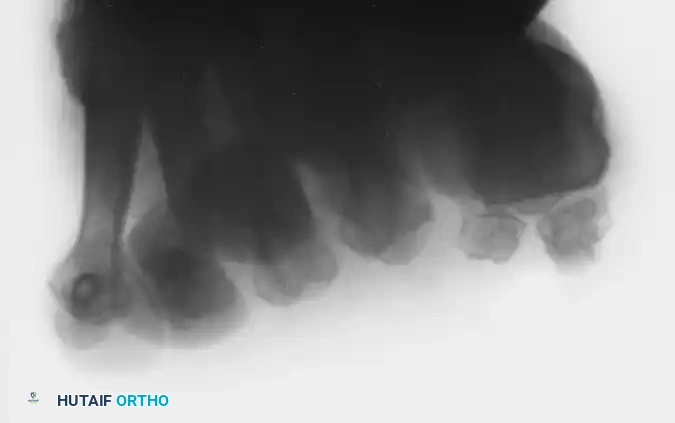

Standard weight-bearing anteroposterior (AP) and lateral radiographs of the foot are required, but the axial sesamoid view is the most critical imaging modality for evaluating the articular surface, the crista, and the presence of fractures or fragmentation.

FIGURE 81-106: Axial sesamoid view demonstrating a distinct fracture of the tibial sesamoid. Note the sharp, irregular radiolucent line differentiating it from a bipartite sesamoid, which typically features smooth, sclerotic margins.